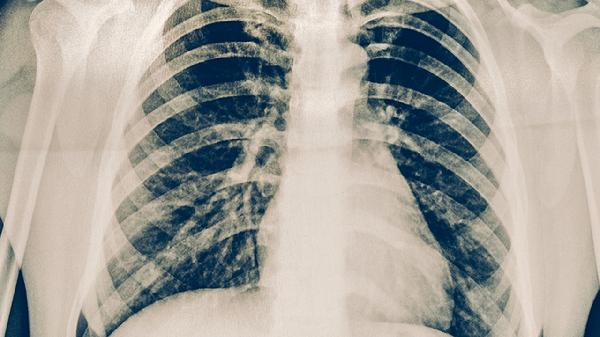

肋骨骨折一个月还会移位吗?

肋骨骨折后1-4周是纤维性骨痂形成期,此时骨折端由纤维组织连接,稳定性相对较差。4-8周是骨性骨痂形成期,骨折端逐渐被新生骨组织替代,稳定性增强。一个月时正处于纤维性骨痂向骨性骨痂过渡阶段,骨折端已有一定稳定性,在正常活动情况下不易发生移位。但若骨折严重、多发性骨折或患者存在骨质疏松等基础疾病,愈合速度可能较慢。

极少数情况下,肋骨骨折一个月后仍可能移位。若骨折端受到较大外力冲击,如剧烈咳嗽、重物撞击胸部或进行高强度体力劳动,可能导致已形成的骨痂断裂。营养不良、糖尿病控制不佳等因素会影响骨痂形成质量,增加移位风险。老年人或长期使用糖皮质激素者骨代谢异常,骨折愈合延迟,一个月时仍有移位可能。

肋骨骨折患者一个月内应避免剧烈运动和重体力劳动,咳嗽时可用手按压患处减轻震动。定期复查X线检查观察骨折愈合情况,若出现胸痛加重、呼吸困难等症状应及时就医。保持均衡饮食,适当补充钙和维生素D有助于骨折愈合。